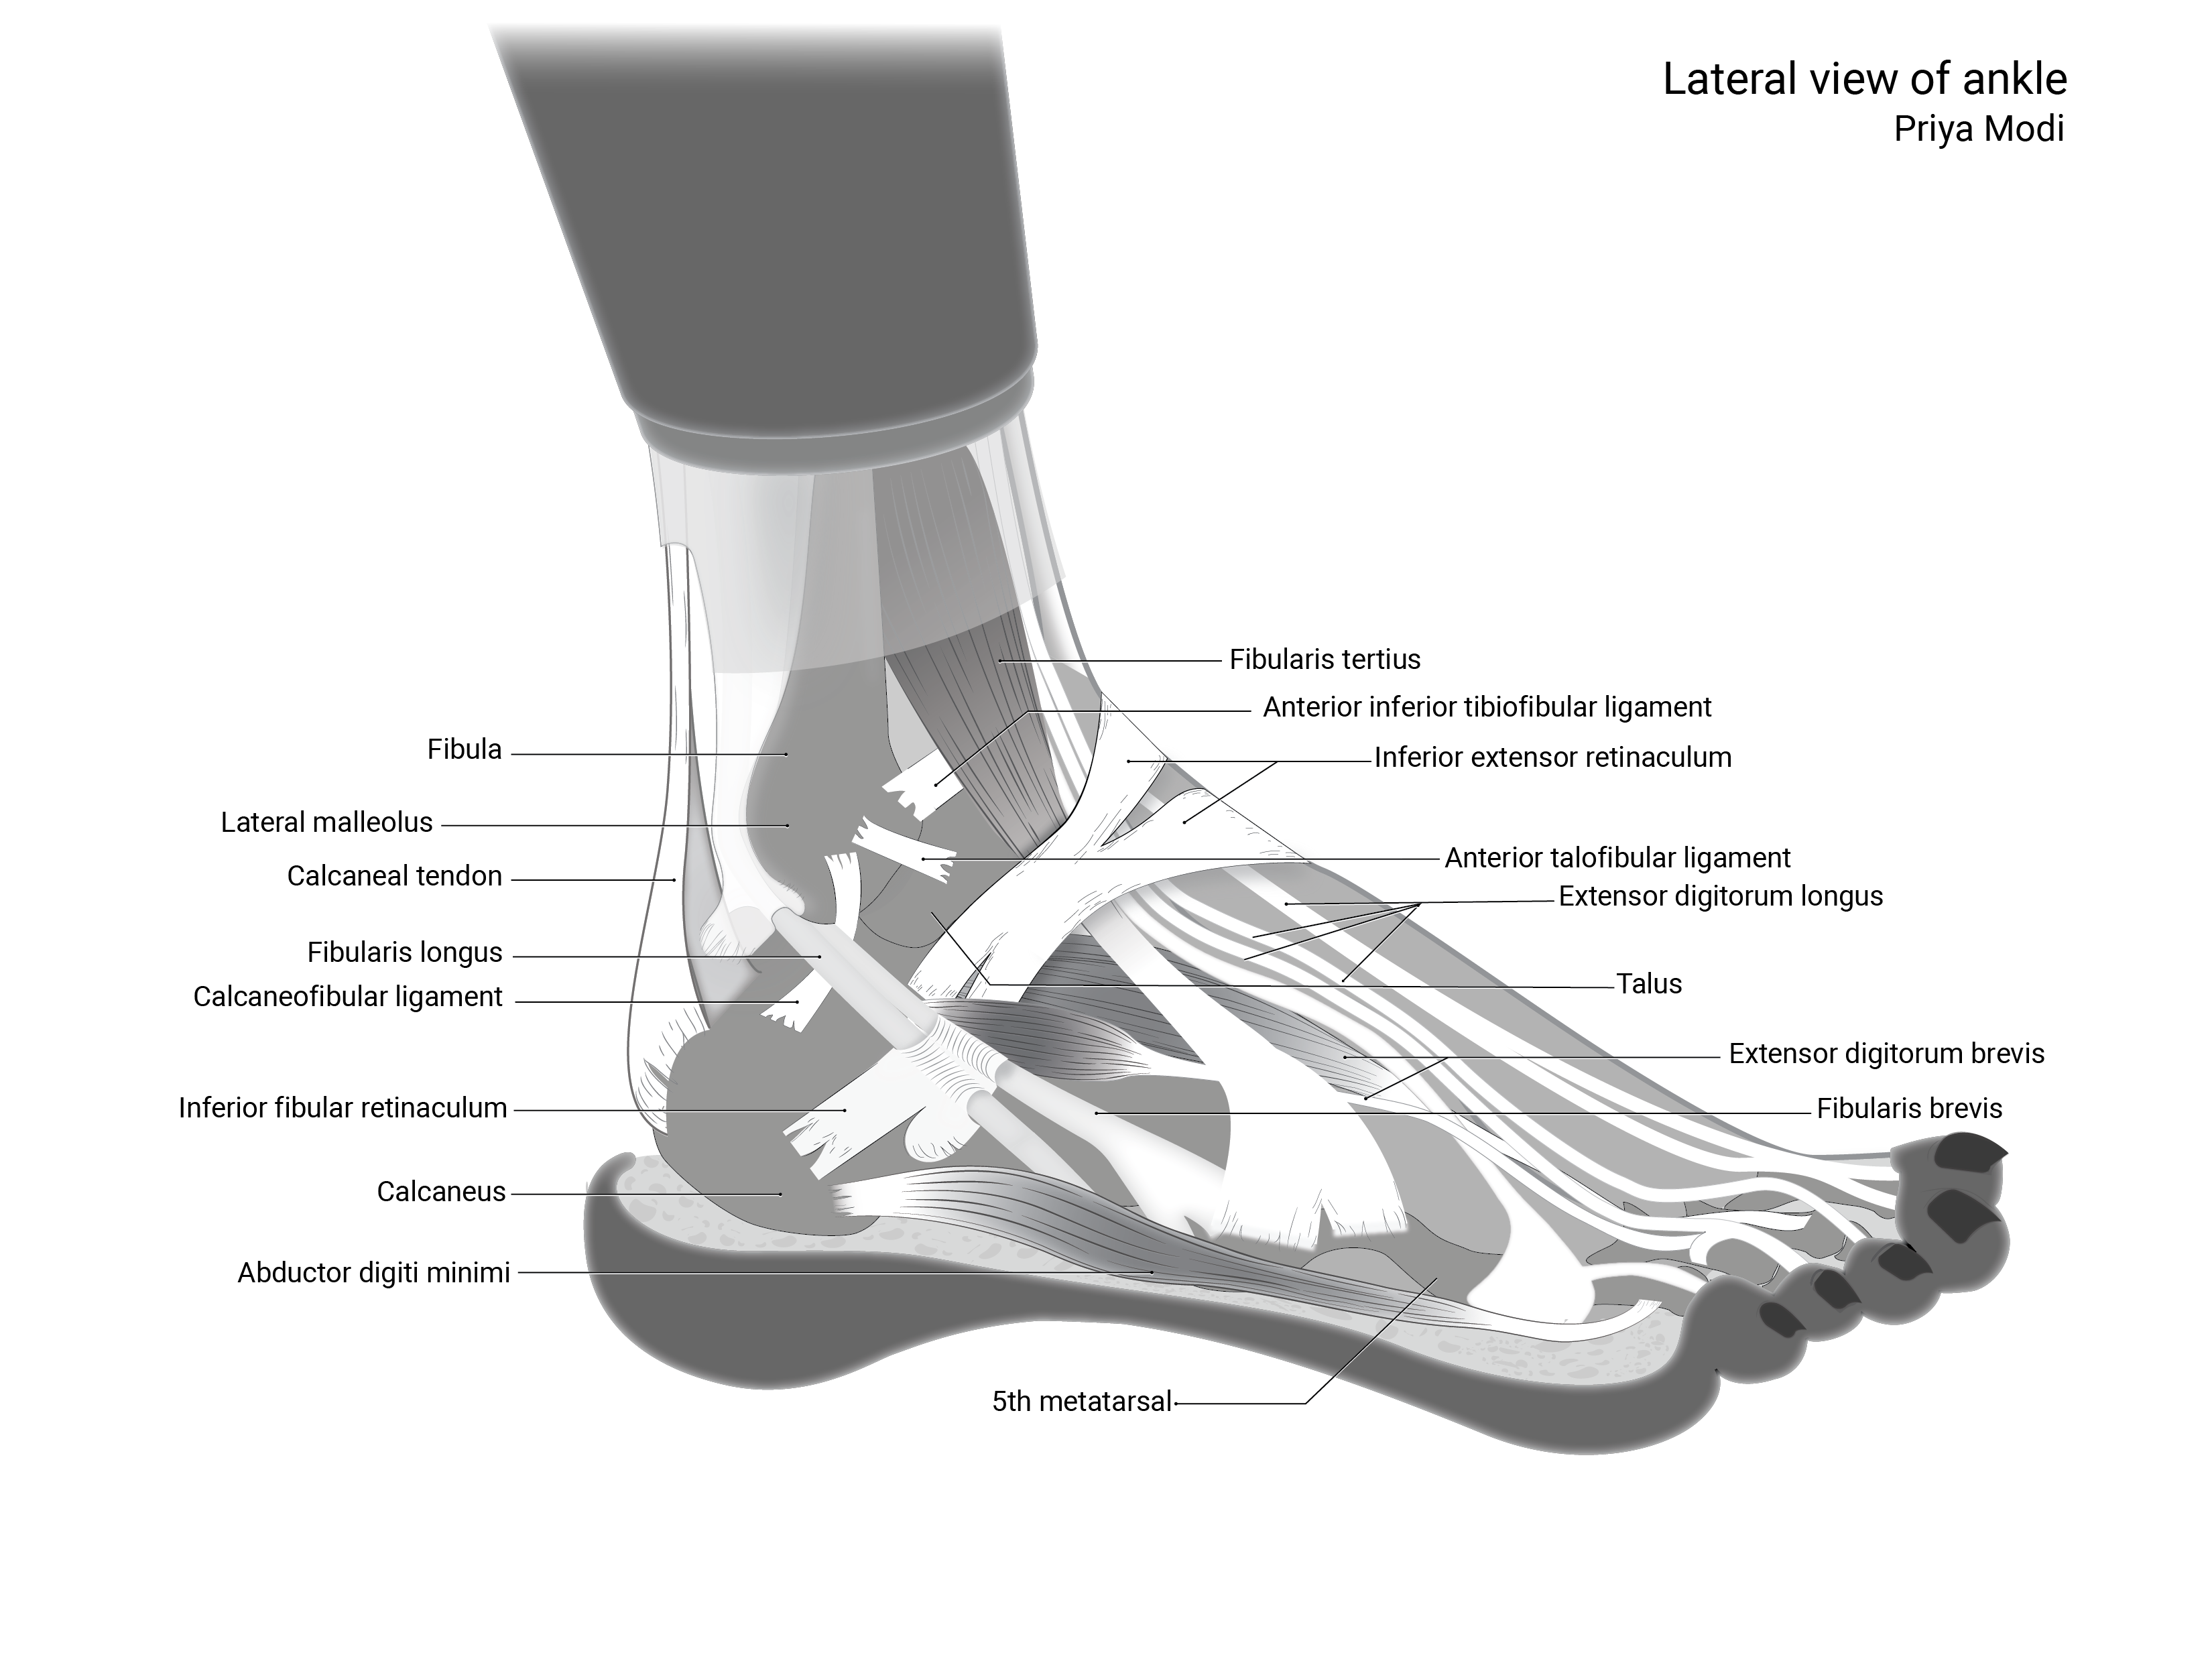

Lateral View of Ankle

2023

Anatomical Illustration | Illustrator | Client: Shelley Wall